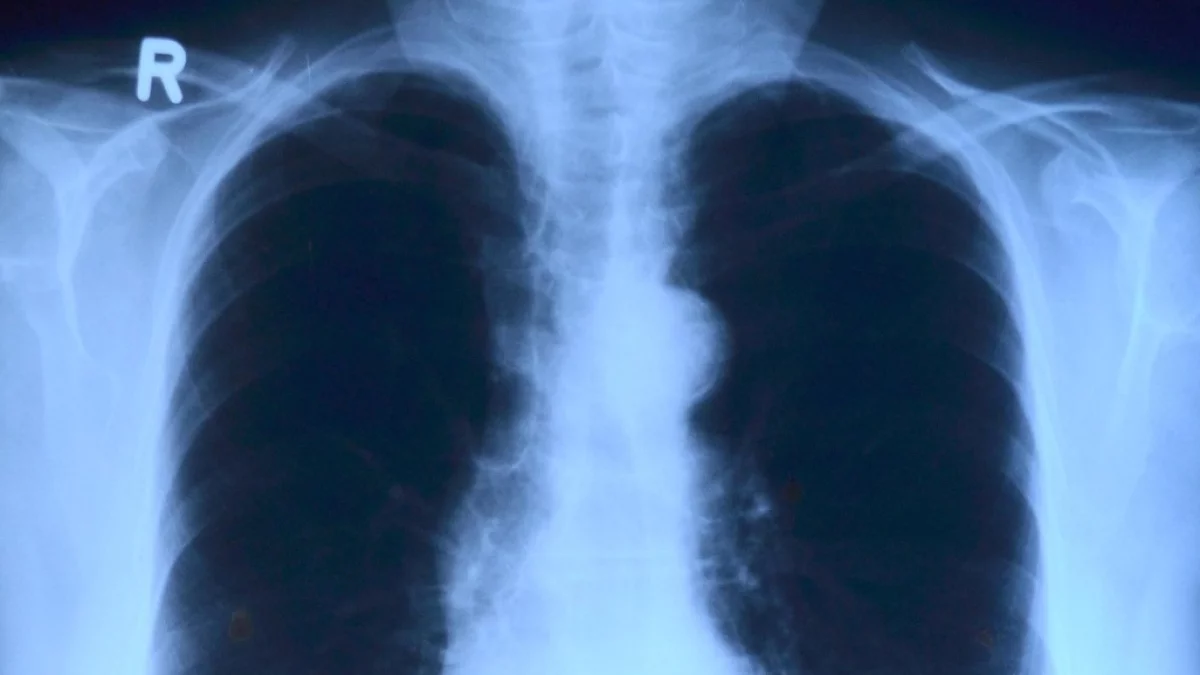

Opóźnienia w opisach badań RTG w szpitalu w Lubartowie – pacjenci zaniepokojeni - Zdjęcie główne

Informacje lubartowskiePacjenci Samodzielnego Publicznego Zakładu Opieki Zdrowotnej w Lubartowie są coraz bardziej zdenerwowani długim czasem oczekiwania na opisy badań rentgenowskich. Według oficjalnej informacji zamieszczonej na kartce w rejestracji, opisy powinny być gotowe w ciągu... 10 dni! Jednak nie ma gwarancji, że po tym czasie opis trafi w nasze ręce!

Chodzi o pacjentów którzy wykonują takie badania w szpitalnej pracowni RTG na zlecenie np. lekarzy ze swoich przychodni. Powinni jak najszybcieć do nich wrócić z opisem badań, który jest podstawą do dalszego leczenia.

- Byłem zaskoczony widząc wiszącą kartkę. Mam tylko nadzieję, że to nie zapalenie płuc - mówi nam Czytelnik, korzystający z rentgenu w ostatnim czasie.